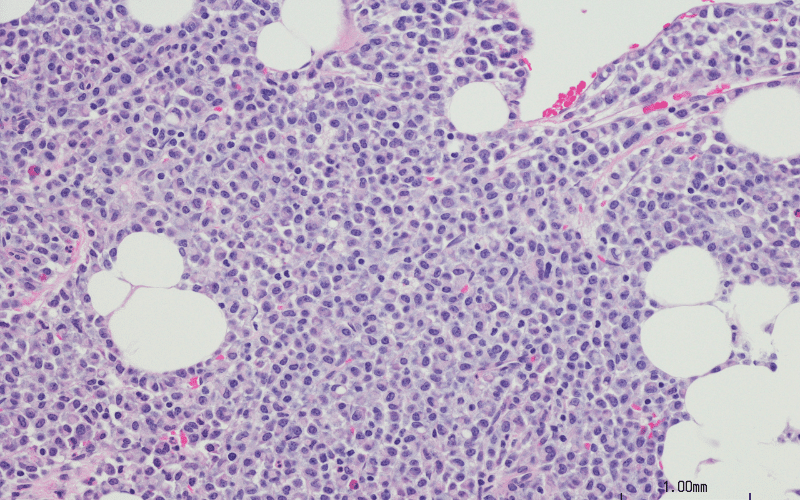

Laboratory investigation revealed a hemoglobin level of 5.5 g/dL, a white blood cell counts of 15900/mL, a platelet counts of 80000/mcL, and a reticulocyte count of 2.3%. Other biochemical parameters, including kidney function, liver function, and serum electrolytes, were within normal range. Abdominal ultrasound showed hepatosplenomegaly. A bone marrow aspiration was performed, which revealed the presence of crinkled paper macrophages in the marrow space as shown in figure 1. A beta-glucosidase test was also recommended, and the levels were found to be 6.2 nmol/h/mg.

Figure 1: Bone marrow biopsy